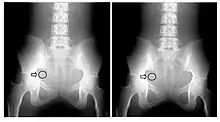

A second parameter to be derived from the transfer characteristic is the dynamic range, which expresses the range of input signals over which the image receptor is sensitive. In the case of CR, its about four orders of magnitude - see Figure 6.3, which shows its transfer characteristic in comparison to the traditional film/screen technology. The result is that under-exposure and over-exposure of regions traditionally seen radiographs are much less of an issue in clinical imaging. This feature of CR is illustrated by the radiographs in Figure 6.4.

Mottle can typically be seen in radiographic images as minute random fluctuations in the greyness of the anatomical details portrayed - see the images in Figure 6.4, for an example. When these fluctuations are large enough, they may obscure subtle changes in image contrast and render details invisible on the image. We will consider the major source of mottle below.